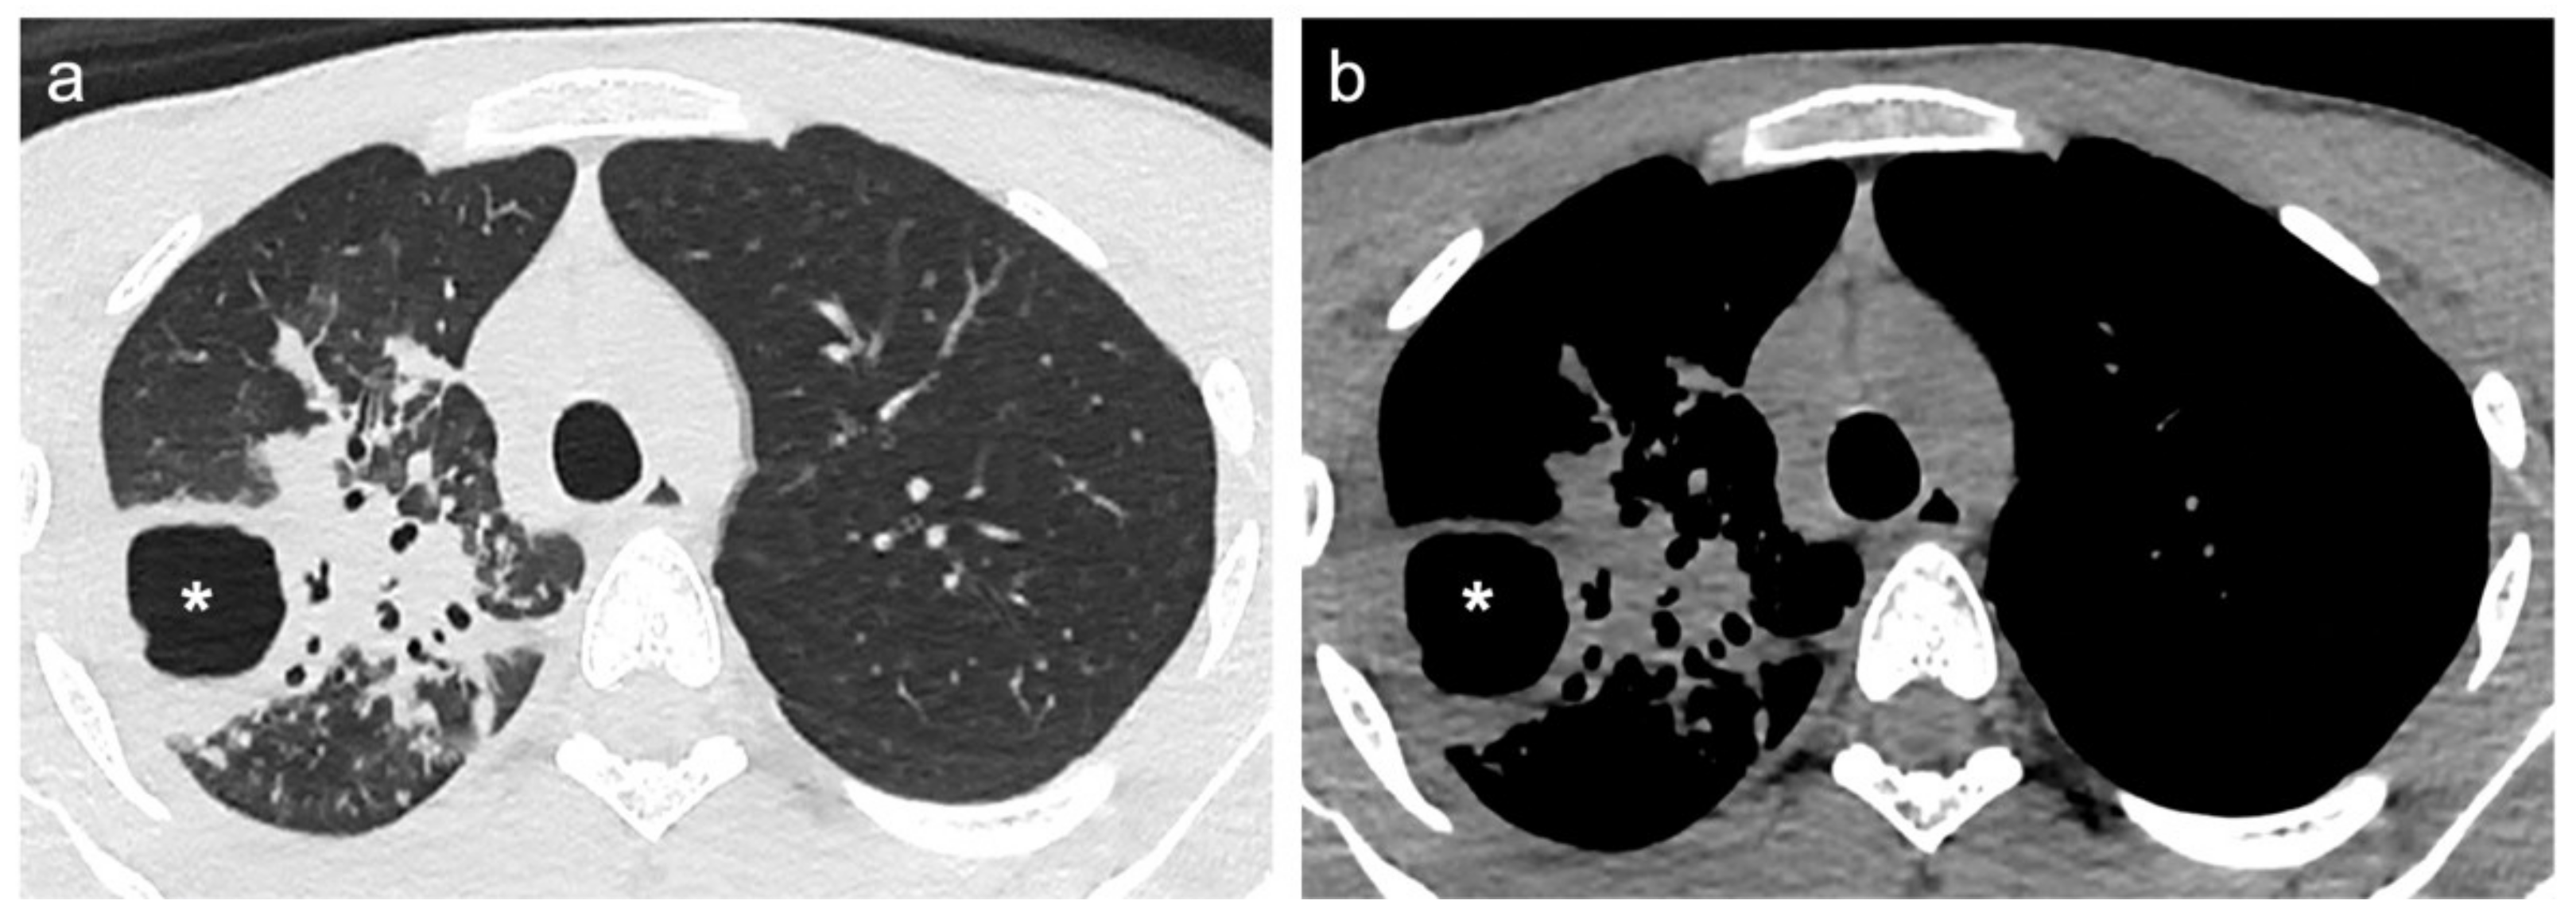

2.3. CT Scans Evaluation and Segmentation Analysis